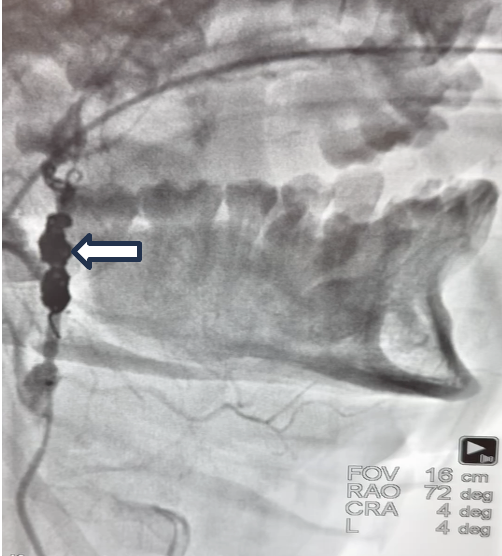

Using a 7 French (Fr) guide catheter and a 5 Fr inner catheter, high radial force coils were deployed and woven into a scaffold, acting as a thrombogenic focus. Complete cross-sectional occlusion was then obtained by deployment of soft coils, successfully achieving hemostasis (Figure 3, Video).

The scaffolding technique (Figure 4) was preferred over other liquid embolization agents for endovascular embolization due to its convenience and readiness, ensuring valuable time savings in an emergency. Post procedure, the patient remained hemodynamically stable and was safely transferred for further trauma management at a higher-level care center.